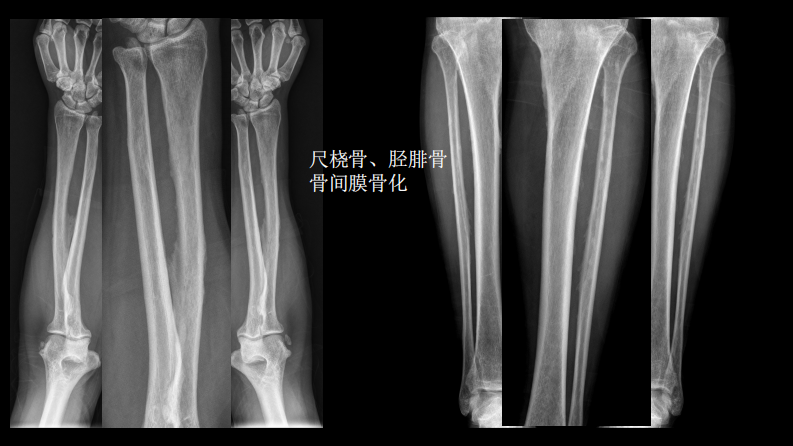

氟骨症的X线CT及MR影像及解读.pdf